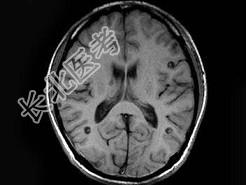

- 单项选择题男,29岁, 头痛不适半个月,MRI扫描如图, 最可能的诊断是 ( )

A、脑转移瘤

B、脑囊虫病

C、脑弓形虫病

D、脑脓肿

E、未见异常